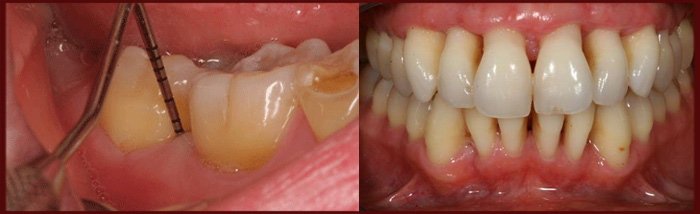

1)عمل جراحی افزایش طول تاج : گاهی روش های جراحی لثه برای فراهم آوردن کارهای ترمیمی و بهبود حالت لبخند لثه ای به کار می رود در حالت لبخند لثه ای دندان ها کوچکتر به نظر میرسند که در واقع طول حقیقی دندان ها نامناسب بوده و به واسطه ی نسوج زیاد لثه ای پوشیده شده است که برای رفع این مشکل ، جراح لثه ، عمل افزایش طول تاج را انجام می دهد که در این درمان ، نسوج اضافه ی لثه برداشته می شود و تا حدی استخوان تغییر شکل داده می شود تا مقادیر بیشتری از ساختمان دندان مشاهده شود . این عمل ممکن است برای یک دندان یا برای هم سطح نمودن خط لثه ای یا دندان های زیادی انجام شود تا نهایتا لبخند وسیع و با حالت طبیعی ایجاد شود . عمل افزایش طول تاج ، حد لثه و استخوان اطرا    ف دندان را تغییر می دهد به طوری که دندان ها بیشتر در دسترس قرار گرفته و قابل ترمیم شوند ، عمل افزایش طول تاج برای بهبود زیبایی انجام می شود .